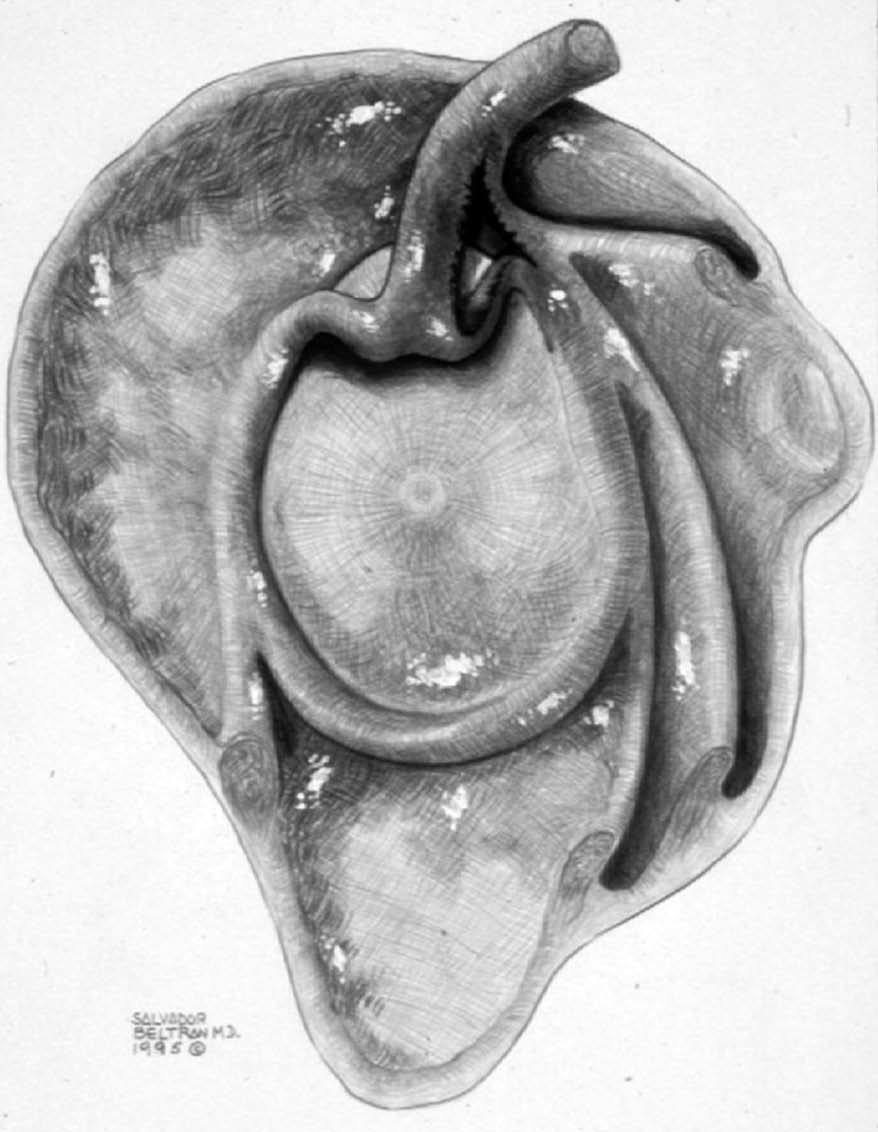

POLPSA (posterior labral periosteal sleeve avulsion)

Esta lesión se asemeja a la ALPSA, pero ocurre en el borde glenoideo posterior. El LG se halla desplazado hacia dentro y por detrás del borde glenoideo posterior. El mecanismo de producción del POLPSA es una dislocación posterior, y por tanto se puede encontrar también un Hill Sachs invertido19 (fig. 14).

. Artrorresonancia axial T1 con supresión grasa donde se observa una rotura del labio glenoideo posterior con desplazamiento posteromedial (flecha). Nótese la situación del labio glenoideo en comparación con una rotura sencilla, no desplazada, que se observa en la figura 13. Obsérvese la presencia de una lesión de Hill-Sachs invertida (cabezas de flecha), en relación con una dislocación posterior con reducción.Lesión de Bennett